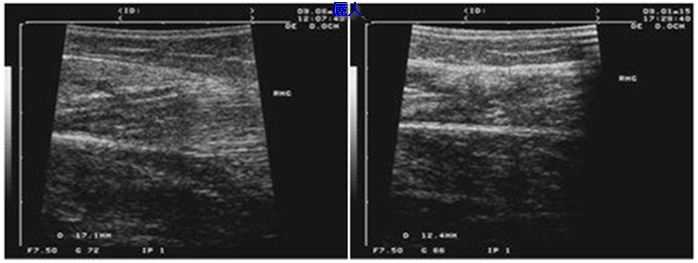

病例三十二:瘦小腿術後五年。

上圖例左圖是瘦小腿前(腿圍是34公分)。右圖是追踨5年後照片,腿圍一直保持在31.5公分。下左圖是術前右側腓腸肌超音波測量圖,腓腸肌厚度是17mm。下右圖是五年後超音波,肌肉厚度是12mm。這五年來小腿一直保持不錯狀態。